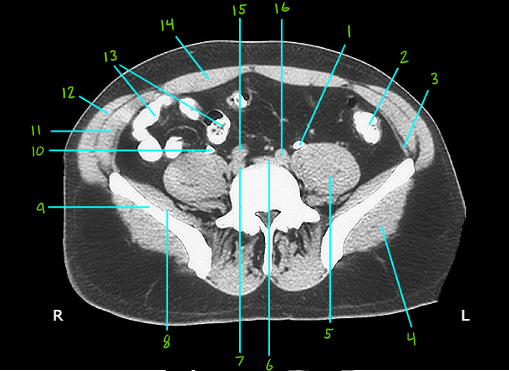

CT Abdomen 2 Flashcards

(14 cards)

What is #1

Left ureter

What is #2

Sigmoid colon

What is #3

Transverse abdominis muscle

What is #4

Gluteus maximus muscle

What is #5

Posas major muscle

What is #6 & 7

R and L common iliac veins

What is #8

Iliacus muscle

What is #9

Ala of the illium

What is #10

Right ureter

What is #11

Internal oblique muscle

What is #12

External oblique muscle

What is #13

Ileum

What is #14

Rectus abdomins ,uscle

What is # 15 & 16

R and L commin iliac arteries